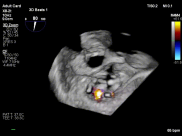

【图片1:术前超声图】

病例1为典型退行性二尖瓣脱垂(DMR),术前超声提示外交界瓣叶明显脱垂,反流程度达重度(4+),伴随活动后气促等心衰症状。由于病变位于“红区”,瓣叶结构复杂、对合不稳定,属于TEER治疗中的高难度类型。